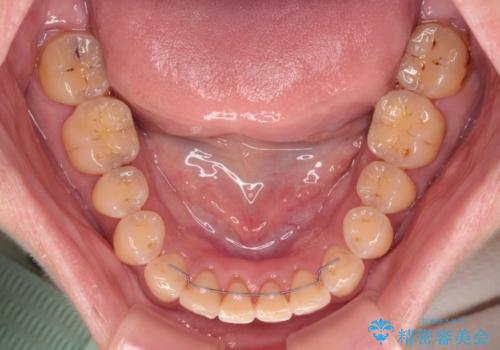

- 審美装置

なるべく早めに治療を終えたいとのことで、補助装置を用いて上顎臼歯を後方に移動させ、同時にワイヤー装置にて整えることとしました。

舌の突出癖が原因で上下の歯に大きなスペースが生じていたため、舌のトレーニングをしっかり行っていただくことで、上顎歯列をスムーズに移動させることができました。